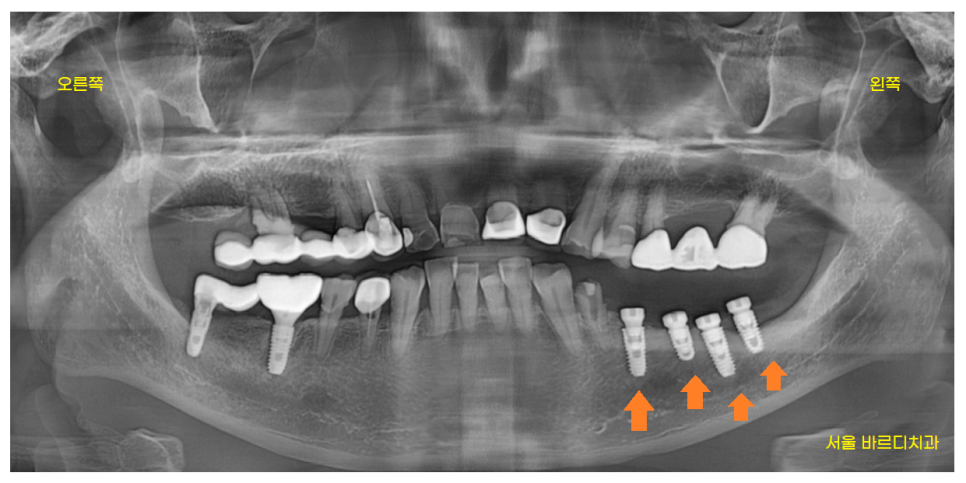

위아래 양쪽으로 치료를 하신 환자분

잇몸뼈가 전반적으로 많이 녹기도 하였고

오래 전 한 보철이 문제가 있엇습니다.

환자분은 왼쪽 아래 오래전에 한 임플란트가

들썩 들썩 흔들려서

식사를 못하고 계신다 하셨습니다.

23.08.23

망월동 치과에서 발치후

왼쪽 아래 임플란트 먼저 수술하였습니다.

재수술인셈이죠.

기존에 있는 임플란트를 제거 후

교체해주는 작업을 진행하였습니다.

왼쪽 아래 임플란트 수술을 끝내놓고

보철을 만들쯔음

사건이 생겼습니다.

23.10.10

오른쪽 위 보철이 빠지셨답니다..!!

임플란트 반대편 치아가 문제가 생기는 경우요.